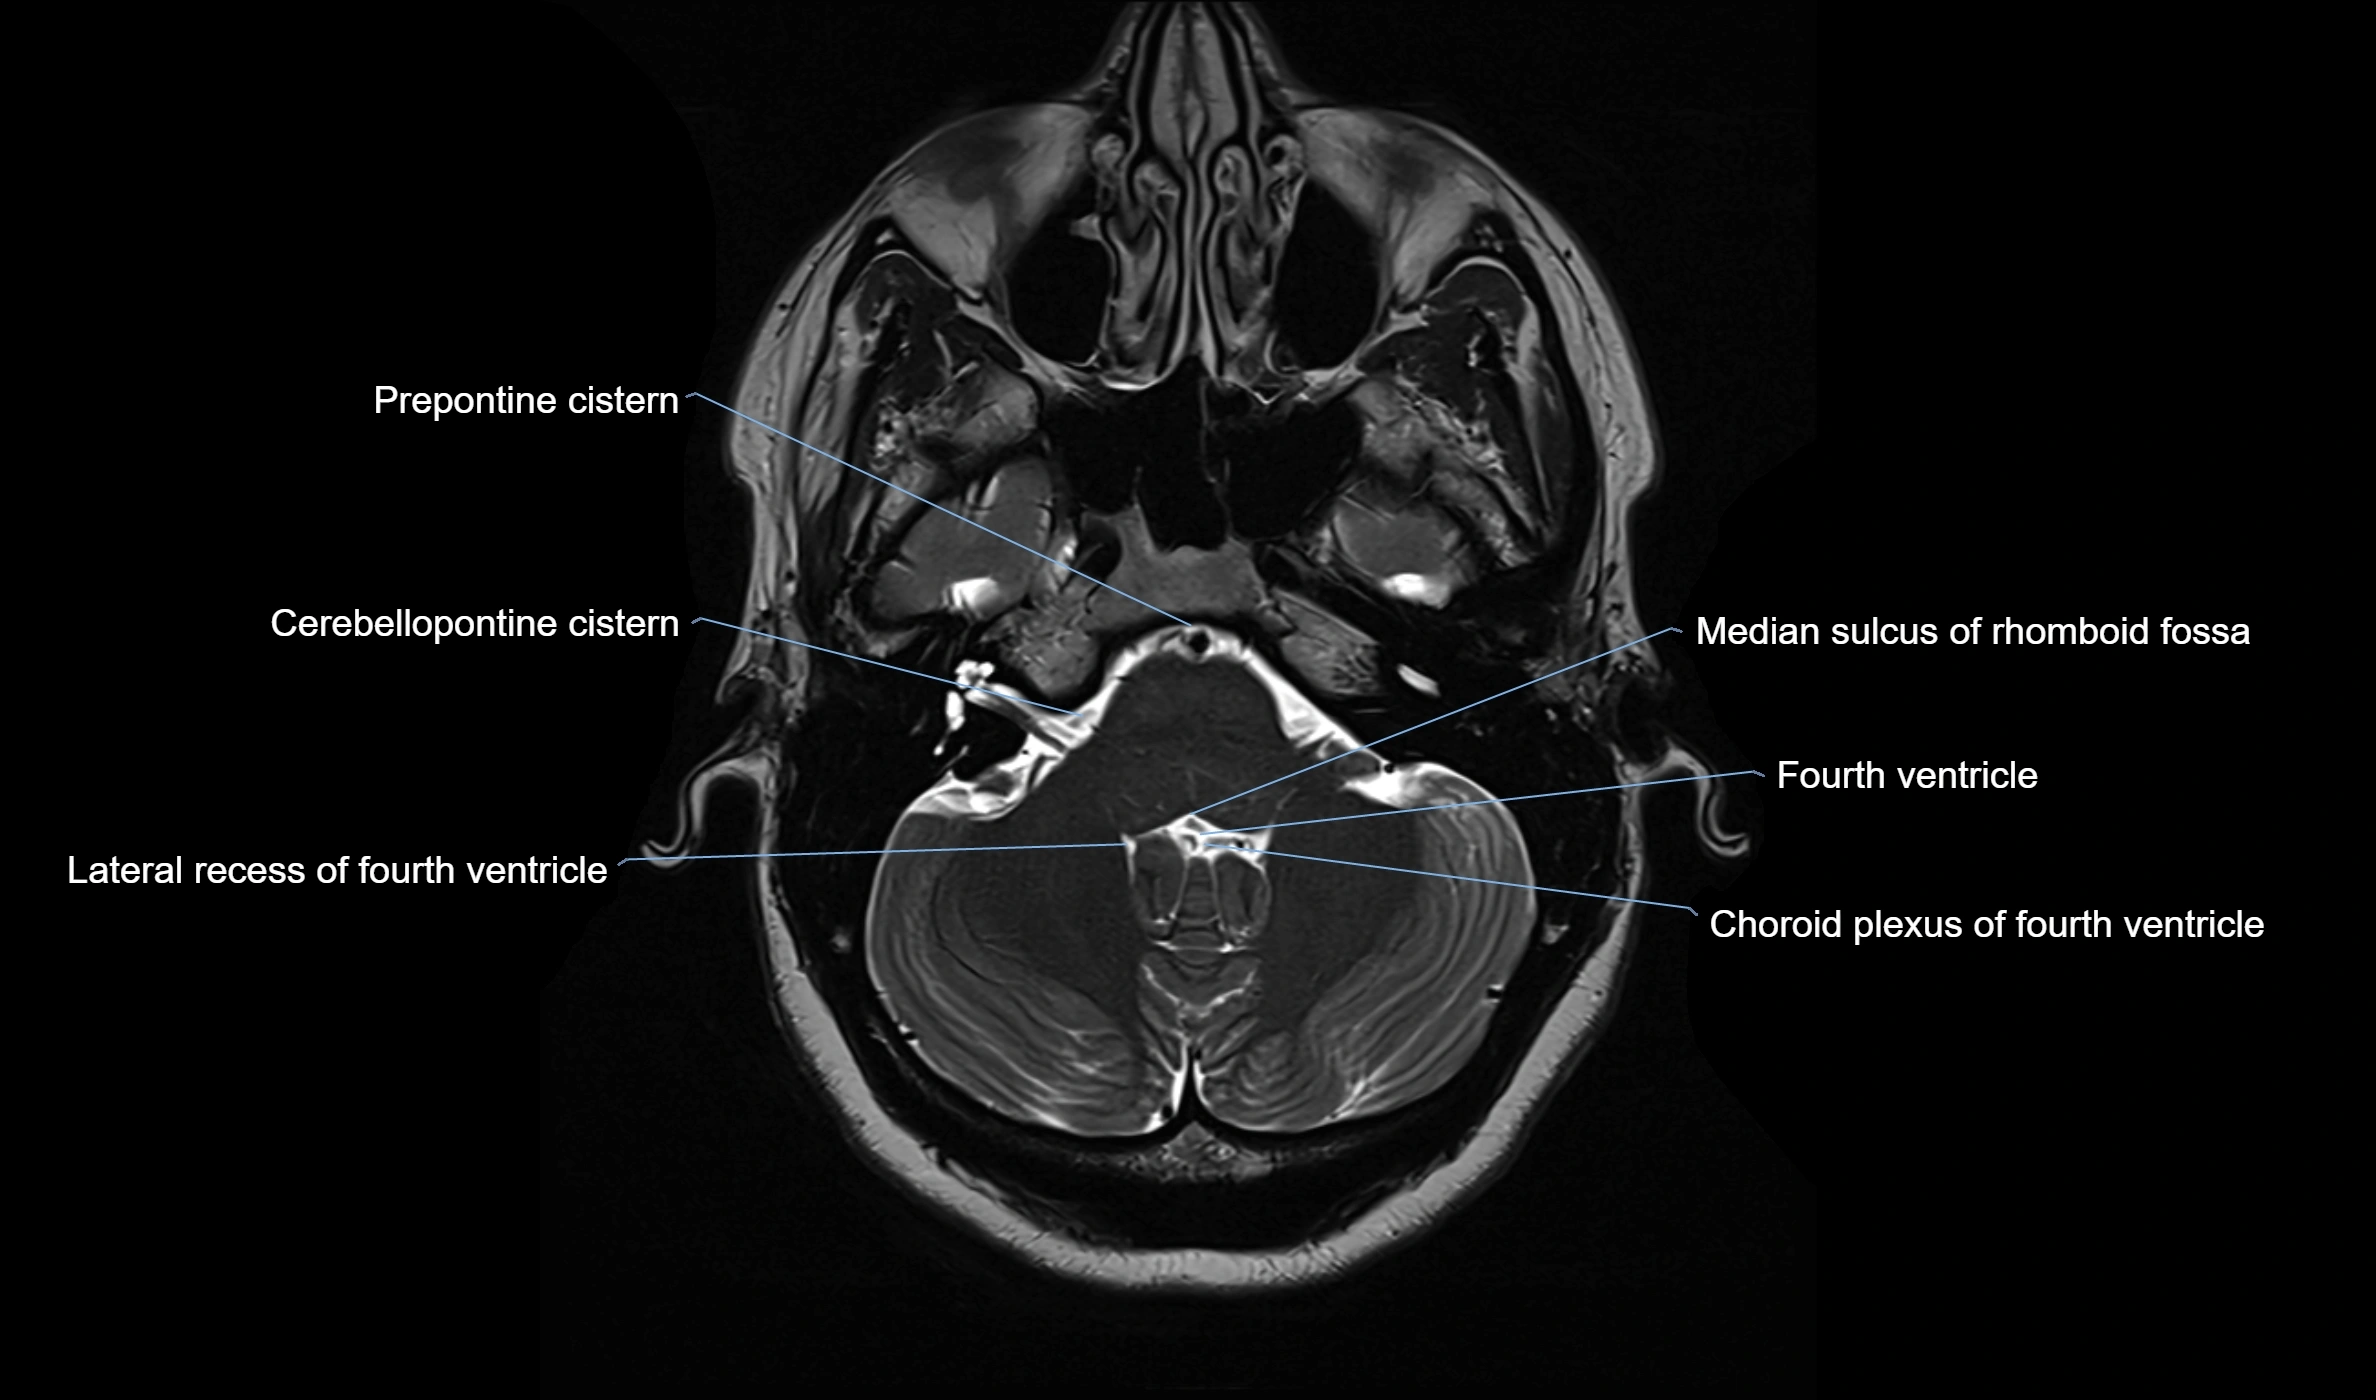

CT Appearance

• The ambient cistern is visualized as a low-density (hypodense) area, similar to other CSF-filled spaces, lateral to the midbrain.

• Blood, masses, or increased attenuation in the cistern may suggest pathology (e.g., subarachnoid hemorrhage, mass effect from tumors or edema).

• Loss of normal cistern outline can indicate mass effect, brain swelling, or herniation.

image